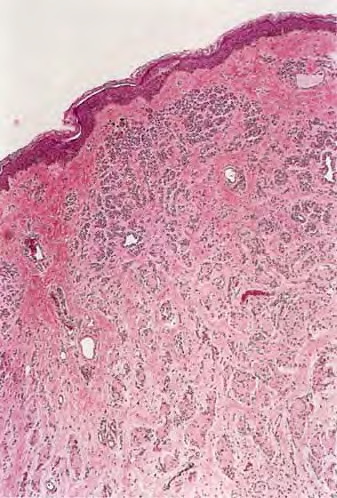

Intradermal Nevus.

Intradermal nevi show essentially no junctional activity. The upper dermis contains nests and cords of nevus cells. Multinucleated nevus cells may be seen in which small nuclei lie either in a rosette-like arrangement or close together in the center of the cell. These nevus giant cells differ significantly in appearance from the irregularly and even bizarrely shaped giant cells that are seen frequently in Spitz nevus and occasionally also in melanoma. As a result of shrinkage during tissue processing, clefts may form between some nests of nevus cells and the surrounding epidermis, as well as stroma, the latter leaving a defect that simulates a lymphatic space and thus mimics lymphatic invasion

Whereas the nevus cell nests located in the upper dermis often contain a moderate amount of melanin (particularly type A cells), the type Band C nevus cells in the mid portion and the lower dermis rarely contain melanin. Type C cells appear spindle shaped, are arranged in bundles, and are embedded in collagenous fibers having a loose, pale, wavy appearance similar to that of the fibers in a neurofibroma, resulting in a "neurotized nevus." Such formations have been referred to as neuroid tubes. In other areas, the nevus cells lie within concentrically arranged, loosely layered filamentous tissue, forming so-called nevic corpuscles that resemble Meissner's tactile bodies . Neurotized nevus cells express the marker S100A6 protein, a form of S100 found in Schwann cells, supporting the hypothesis that maturation in these lesions recapitulates some features of Schwann cell differentiation .